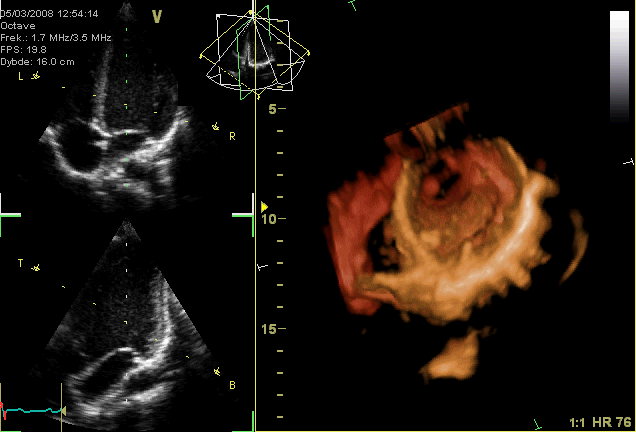

![]() |

| Kalp diyagramı: 1. Sağ atrium (Atrium dextra), 2. Sol atrium (Atrium sinistrum), 3. Superior vena kava (Vena cava superior), 4. Aort, 5. Pulmoner arter, 6. Pulmoner ven, 7. Mitral kapak, 8. Aort kapağı, 9. Sol ventrikül, 10. Sağ ventrikül, 11. Inferior vena kava (Vena cava inferior), 12. Triküspit kapak, 13. Pulmoner kapak |